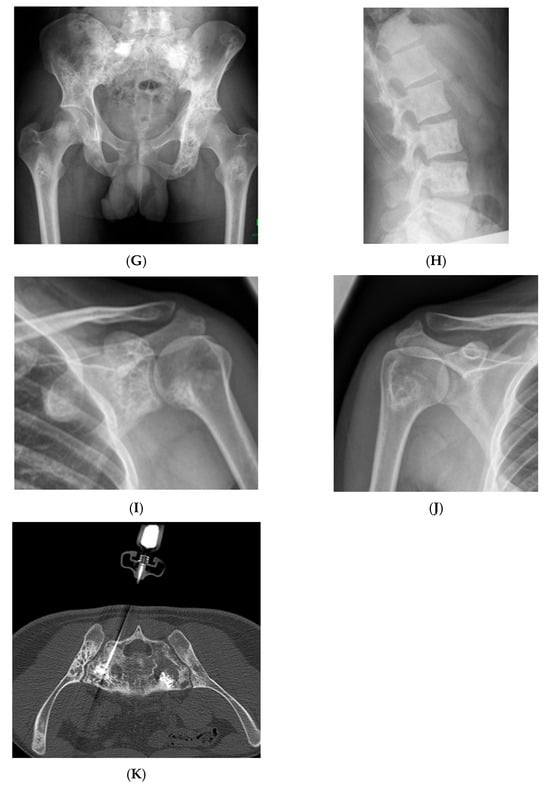

Figure 8.

Multiple haemangiomas. (A) Coronal T1W MRI whole body with side-by-side coronal STIR MRI whole body showing multiple haemangiomas at the vertebral column, pelvis, and proximal femora. (B) Axial T1W Pelvis MRI and (C) STIR Pelvis MRI, further detailing the pelvis lesions. (D) Sagittal T1W Spine MRI with spine haemangiomas. (E) Sagittal T2W Spine MRI with spine haemangiomas. (F) Sagittal STIR Spine MRI with spine haemangiomas. (G) Plain radiograph, pelvis. (H) Plain radiograph, lumbar spine. (I) Plain radiograph, left shoulder. (J) Plain radiograph, right shoulder. All radiographs showcase the corresponding appearances of the lesion on plain films. (K) Axial CT pelvis with biopsy-proven haemangioma at the right hemi-pelvis.